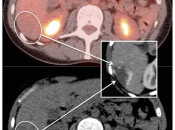

If, however, the finding does not fit a clinical picture, then we should be very cautious before reflexively reporting it as “suspicious for malignancy”.  In these cases, we must first exhaust all other potential explanations for the finding.  [Fig. 1]

Despite the strong desire for quantification of metabolic activity via the SUV, the most accurate means of distinguishing malignancy from benignity ultimately relies on comparison of a potential lesion’s activity to the background uptake on the scan, its “relative uptake”.

Comparison is most frequently made to uptake within the liver, the mediastinal blood pool or to the organ within which a potential lesion is located.

This comparison can be made by visual assessment or by SUV analysis (comparing the SUV maximum of the lesion with the SUV mean of the liver, blood pool or solid organ).